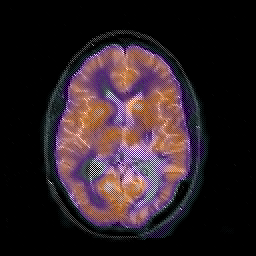

Glioblastoma multiforme overlay -- Slice #29

[Home][Help][Clinical][Tour 1][Tour 2][Tour 3] Slice 29